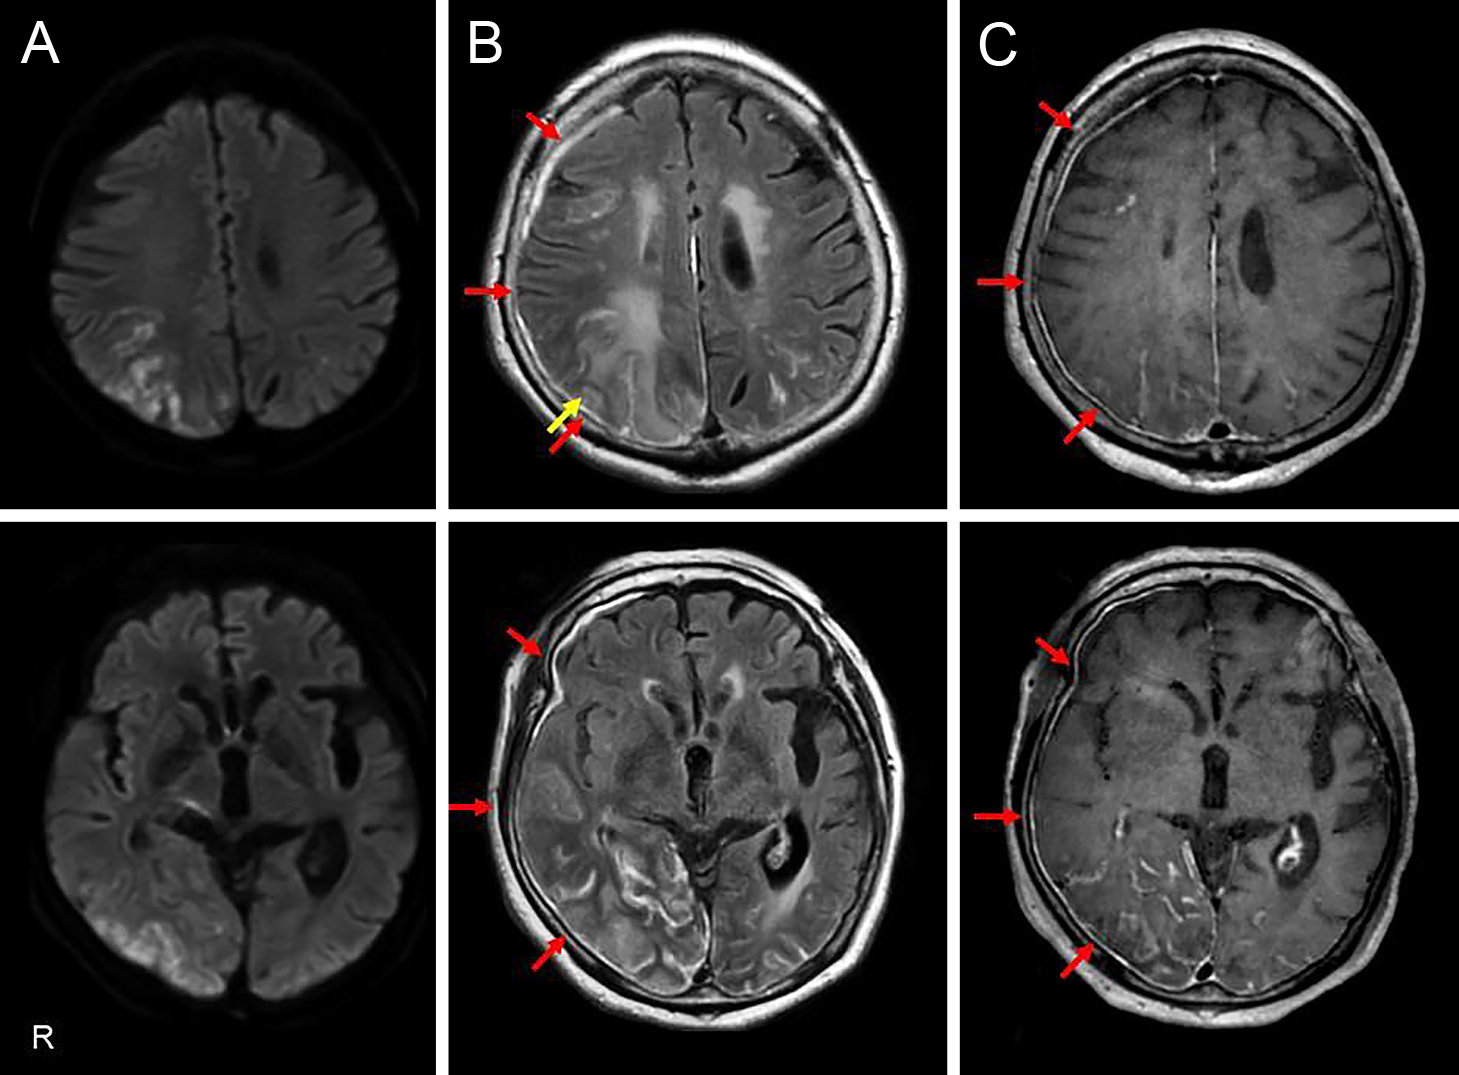

Claustrum signを呈したfebrile infection related epilepsy syndrome(FIRES)の55歳女性例

Febrile infection-related epilepsy syndrome (FIRES) with the claustrum sign in a 55-year-old woman: a case report

赤尾 剛, 市川 大, 藤盛 寿一, 中島 一郎

Go Akao, Dai Ichikawa, Juichi Fujimori, Ichiro Nakashima

2026/03/11